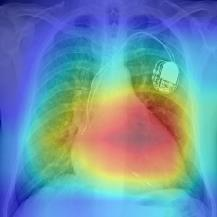

Thoracic disease detection from chest radiographs using deep learning methods has been an active area of research in the last decade. Most previous methods attempt to focus on the diseased organs of the image by identifying spatial regions responsible for significant contributions to the model's prediction. In contrast, expert radiologists first locate the prominent anatomical structures before determining if those regions are anomalous. Therefore, integrating anatomical knowledge within deep learning models could bring substantial improvement in automatic disease classification. This work proposes an anatomy-aware attention-based architecture named Anatomy X-Net, that prioritizes the spatial features guided by the pre-identified anatomy regions. We leverage a semi-supervised learning method using the JSRT dataset containing organ-level annotation to obtain the anatomical segmentation masks (for lungs and heart) for the NIH and CheXpert datasets. The proposed Anatomy X-Net uses the pre-trained DenseNet-121 as the backbone network with two corresponding structured modules, the Anatomy Aware Attention (AAA) and Probabilistic Weighted Average Pooling (PWAP), in a cohesive framework for anatomical attention learning. Our proposed method sets new state-of-the-art performance on the official NIH test set with an AUC score of 0.8439, proving the efficacy of utilizing the anatomy segmentation knowledge to improve the thoracic disease classification. Furthermore, the Anatomy X-Net yields an averaged AUC of 0.9020 on the Stanford CheXpert dataset, improving on existing methods that demonstrate the generalizability of the proposed framework.